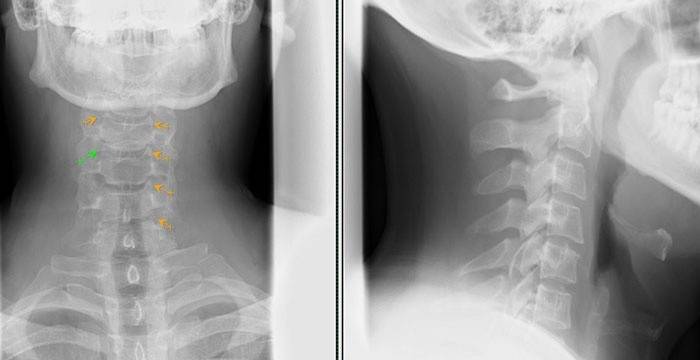

diagnostika

Ak chcete určiť, ako liečiť osteochondrózu krčnej chrbtice, mali by ste sa spojiť s lekárom, špecialistom v tejto oblasti, a podstúpiť diagnózu. Ak pôjdete do lekárskeho zariadenia, navštívte lekára, ktorý vás odporučí špecialistovi (môže to byť osteopat, neurológ alebo vertebroológ).

Ako diagnostika sa môžu použiť tieto metódy:

- rádiografiu, Táto možnosť výskumu je užitočná v počiatočných štádiách vývoja choroby, keď sú pozorované iba praskliny, malé zmeny v štruktúre.

- Počítačová tomografia (CT), Táto diagnostická metóda vám umožňuje určiť prítomnosť zmien na stavcoch.Ale na stanovenie veľkosti prietrže nie je možné dosiahnuť stupeň kompresie stavcov.

- Zobrazovanie pomocou magnetickej rezonancie (MRI), Ideálna voľba pre diagnostiku osteochondrózy krčnej chrbtice, pretože všetky zmeny v štruktúre sú zreteľne rozlíšiteľné, je možné určiť smer rastu prietrže, jej veľkosť.